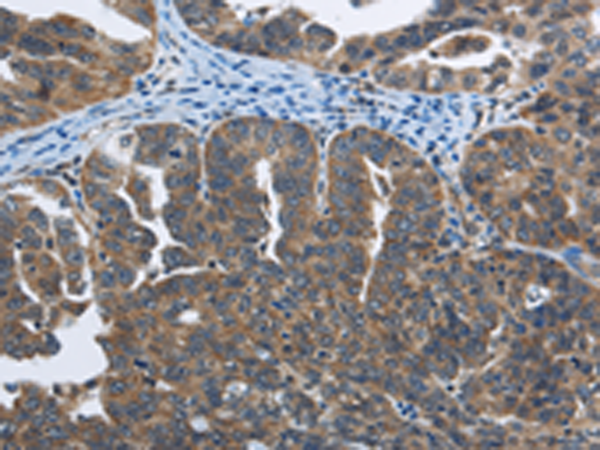

中文名稱:兔抗SYT3多克隆抗體

英文名稱: Anti-SYT3 rabbit polyclonal antibody

ELISA, IHC

IHC positive control:

Human ovarian cancer and human cervical cancer

IHC Recommend dilution:

50-100